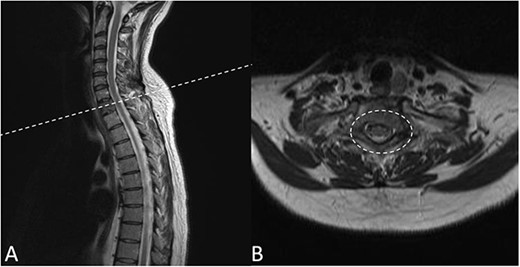

Preoperative magnetic resonance imaging (MRI) and preoperative CT scans helped determine Tokuhashi, Tomita and ESCC scores, which was vital to plan treatment for this patient (Figs 1 and 2). The occurrence of the lesion occurring in T2 indicated an anterior approach. This would be safer than a posterior approach as the ESCC grade of 2 made it surgically challenging to resect tumour and lay instrumentation around the spinal cord. An anterior approach also avoids cervico–thoracic junction fusion.

Preoperative MRI Scan December 2019. (A) Sagittal view of oligometastatic lesion at T2 vertebral body. (B) ESCC grade 2 determined as there is spinal cord compression, but with cerebrospinal fluid visible around the cord.